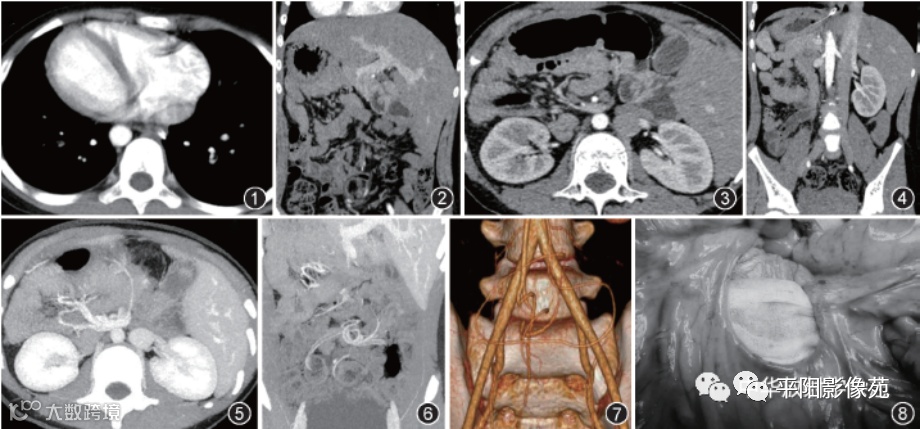

儿童罕见先天性肠系膜裂孔疝并完全内脏反位影像表现一例。

患儿男,9岁,因间断腹痛伴呕吐1天于2020年1月就诊于天津市儿童医院。患儿入院前1天出现无明显诱因下腹痛伴呕吐3~4次,胃内容物不含咖啡样物质。患儿无明显发热、寒战,大小便正常,否认家族史和传染病史。急诊超声提示全内脏转位,不除外肠扭转。体检:神志清,反应可,发育正常,营养中等,蜷缩体位,呼吸促,口唇周无发绀。腹胀,未见肠型及蠕动波,全腹部散在压痛,下腹部压痛感明显,无明显肌紧张和反跳痛,未及腹部包块,肠鸣音存在。实验室检查正常。

CT检查显示心脏、胸腹部大血管及腹腔实质脏器完全性反位(图1~3),右中腹部肠管间见无肠黏膜异常含气空腔,考虑腹内疝并肠管缺血;前方可见固定小肠襻成“C”字形,肠系膜上动脉围绕上静脉旋转,肠系膜上静脉及门静脉增粗,近段小肠扩张积液(图2,3),脾脏形态不规则伴数量异常(图4);最大密度投影及容积再现技术重组图像示肠系膜根部血管走行异常并呈“缆绳征”,远端分支血管异常旋转(图5~7)。诊断结果考虑:全内脏反位;肠扭转;腹内疝并肠管缺血不除外。术中见肠系膜上动脉与肠系膜下动脉间系膜缺如(图8),右侧脏层腹膜局限性缺如,由2条肠系膜动脉围绕形成一个巨大肠系膜裂孔,最大径约12 cm×10 cm,大部分小肠及部分结肠疝入其中并顺时针扭转540°,肠管暗红色,此段肠管复位后颜色逐渐红润,予以保留,同时修补巨大肠系膜裂孔。